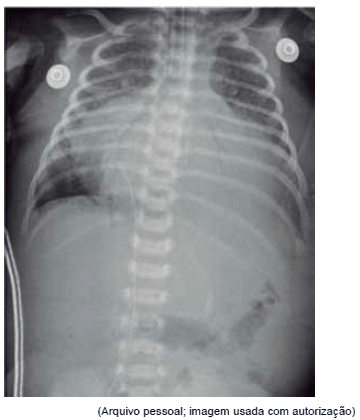

Paciente foi transferido de urgência em vaga zero de UBS para pronto-socorro cardiológico sem história de cardiopatia congênita prévia. Mãe refere que nasceu sem intercorrências, de parto normal, e teve alta no segundo dia de vida. Notou que sua criança tinha dificuldades às mamadas e ficava roxo aos esforços. Após exame físico e cuidados imediatos de intubação orotraqueal, cateter venoso central e sonda nasogástrica, foram feitos os seguintes exames:

Qual é o diagnóstico mais provável?